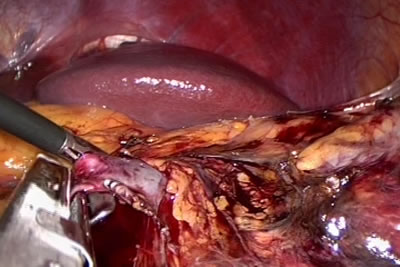

Обработка сосудистой ножки левой почки.

Почечная вена прошивается аппаратом рядом скрепок.